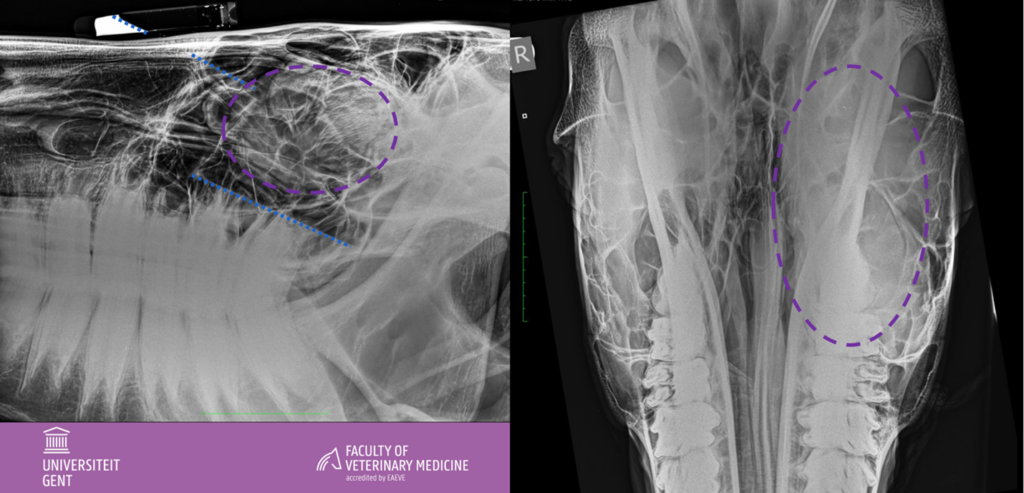

Radiografieën van het hoofd (latero-laterale opname en dorsoventrale opname):

Gebilobeerde goed omschreven weke delen massa gesuperponeerd op de linker caudale maxillaire sinus, geassocieerd met het ethmoid (paarse cirkel). De osseuze structuur van de linker caudale maxillaire sinus blijft behouden, toch zijn de septae minder duidelijk aflijnbaar door de weke delen massa.

Weke delen opaciteit met een vocht-vloeistof lijn ter hoogte van de conchofrontale sinus en thv de caudale maxillaire sinus (blauwe lijnen parallel met contrastbuisje vastgeplakt dorsaal op het hoofd).